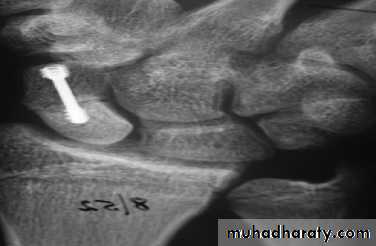

After that either the fracture united with pain free or end with non union and in this case need bone graft and internal fixation by herbert screw.

2-Displaced fractures can also be treated in plaster, but the outcome is less predictable. It is better to reduce the fracture openly and to fix it with a compression screw.